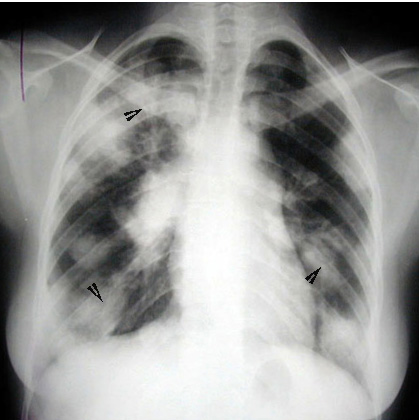

Large nodules with air bronchogram (arrowheads).

Bilateral hilar and paratracheal adenopathy.

Appearance often mistaken for metastatic disease.